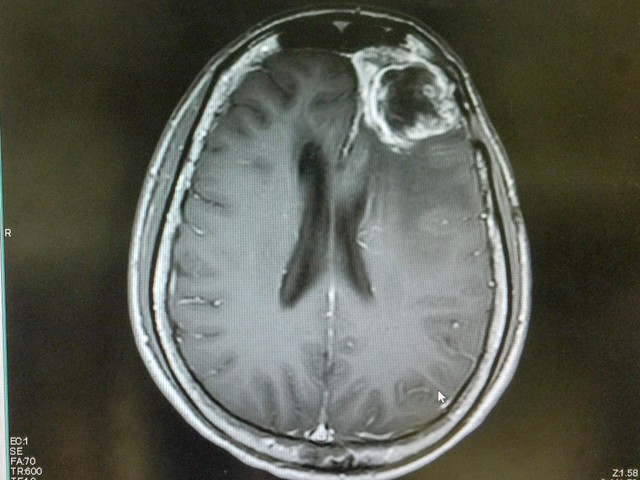

Agydaganat